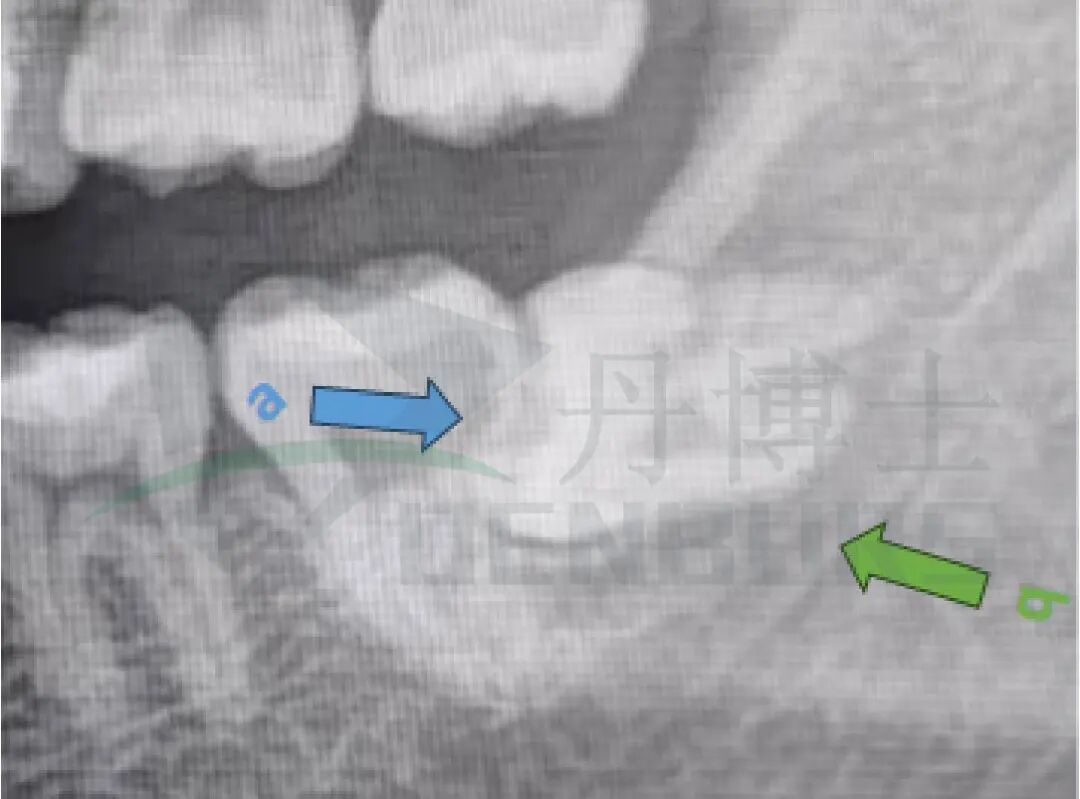

全景片显示:38近中水平高位阻生,37远中邻面部分透射影。

阻力分析

阻生齿案例-04.jpg

• 龈瓣覆盖: 牙龈阻力

• 远中骨覆盖:骨阻力

• 近中部分阻碍邻牙:牙冠阻力

• 临近的解剖结构:37邻牙,下牙槽神经管